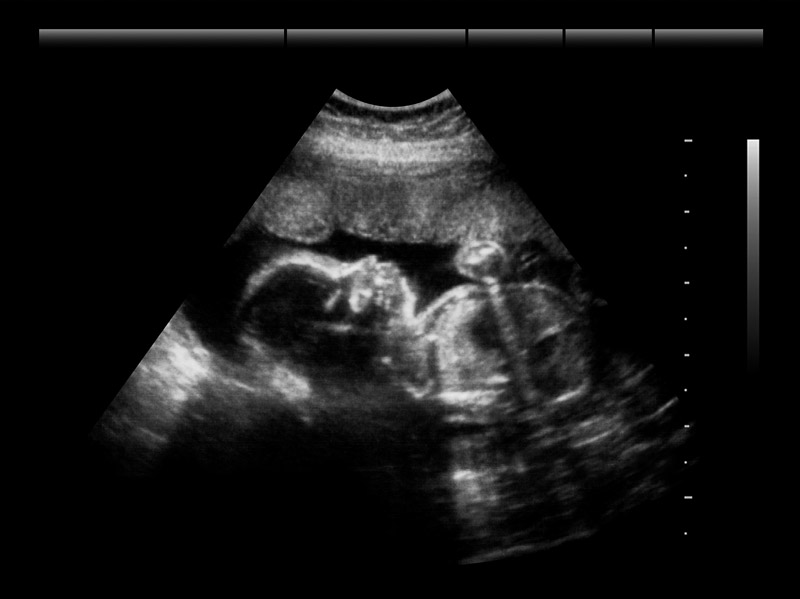

超声波有较强的穿透能力。图 3–3–3 中技术员用超声波探伤仪检测钢结构的缺陷。图 3–3–4 中医生用 B 型超声波观察母体中胎儿的发育情况。